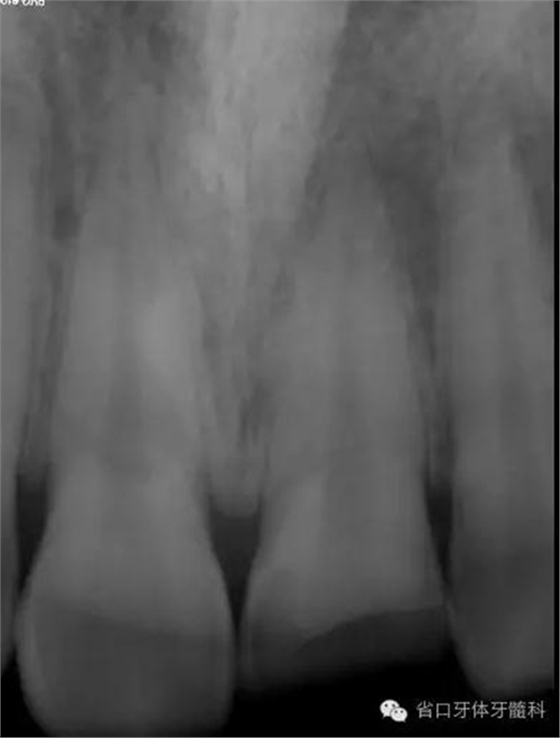

術(shù)前X線片

X線片示21冠折,根段未見明顯牙折影像。

初步診斷:21冠折